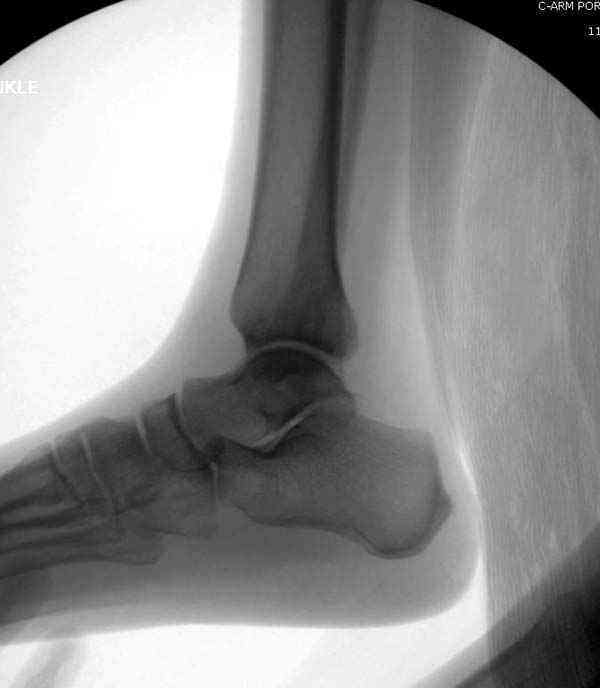

Здесь несколько частных случаев: перелом голеностопа со сравнительными снимками и разрыв синдесмоза, а также медиальная Hook пластина.

Нет первичных снимков, перелом очень низкий и под большим сомнением диагноз разрыва синдесмоза. Медиальная сторона отрепонирована на "хорошо" и, по-видимому, прорезание проволоки произошло во время операции. Без снимков трудно судить о высоте малоберцовой, а лодыжка находится в варусе. Лагирование получилось, но возле тонких шурупов передне-задний шуруп выглядит немного тяжеловато.

Согласен с Антоном по поводу КТ при переломах лодыжек, и всегда пользуюсь ЭОПом для контроля анатомичности репозиции.